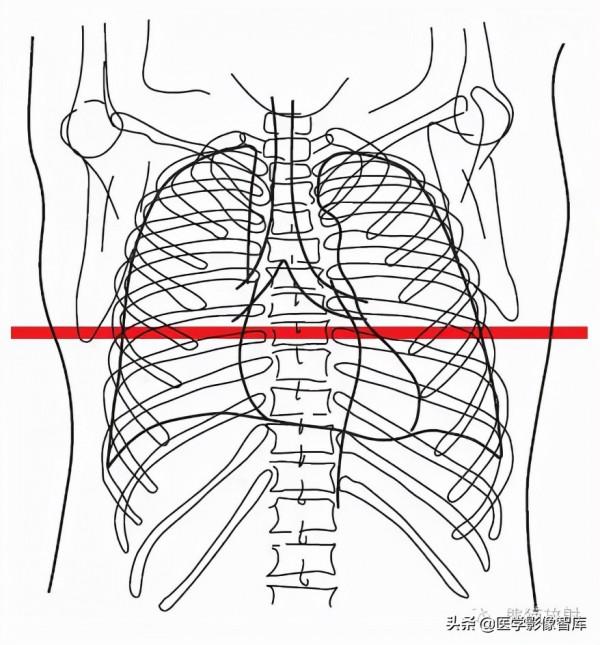

胸部